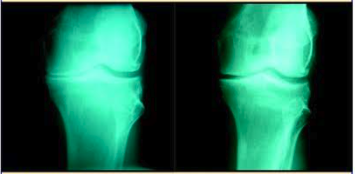

The Center for Regenerative Medicine (CRM) is paving the way with state-of-the-art, non-surgical treatments to help patients regain quality of life. In order to educate the public about all the non-surgical solutions, CRM created The Knee Diaries. Here is an excerpt from The Knee Diaries: "Patient is a 61-year-old male with the chief complaint of knee pain who visited The Center for Regenerative Medicine. He was diagnosed with bone-on-bone osteoarthritis of the left knee, causing him much pain and discomfort. He was informed that only a total knee replacement could help him. He is otherwise healthy. On exam, he had point tenderness to the medial side of the left knee (medical lingo: inner side). An X-ray showed severe arthritis of the knee (X-ray on the left). Patient started receiving treatments at The Center for Regenerative Medicine. Today, he is feeling much better (X-ray on the right).

"This is how it works: The Physician introduces biologics into the damaged arthritic knee by means of a precise injection. This process is followed by several other modalities, including Collateral Artery Flow Exercises, in order to accelerate the process. Depending on the tissue damage, severity of the condition and the size of the joint that needs to be injected, patients will normally need anywhere from two to four treatments to improve. There is no downtime and patients can return back to their normal activities soon after (always adhering to common sense ). The treatments help most muscular-skeletal problems such as low back pain, shoulder pain, whiplash, sciatica, tendinitis, sprains, torn ligaments and cartilage damage."